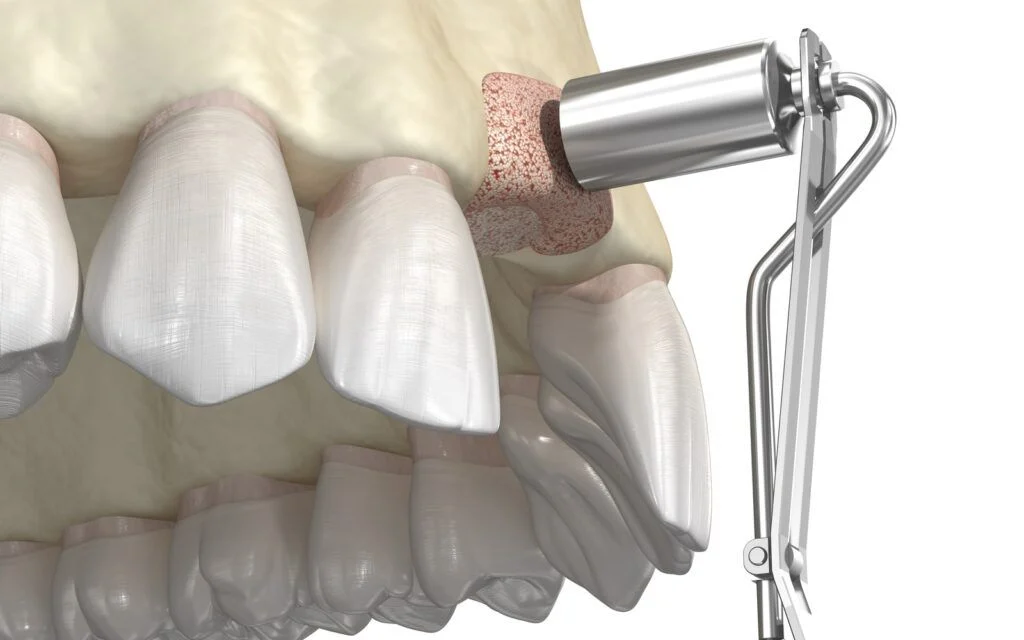

What Is a Sinus Lift?

- Necessary for implants in the upper back jaw, where sinuses may limit bone height.

- Bone is added beneath the sinus membrane, lifting it to make room for the graft.

- Can be done before or at the same time as implant placement, depending on bone availability.

- Healing takes 6 to 9 months, though some cases may allow simultaneous implant placement.